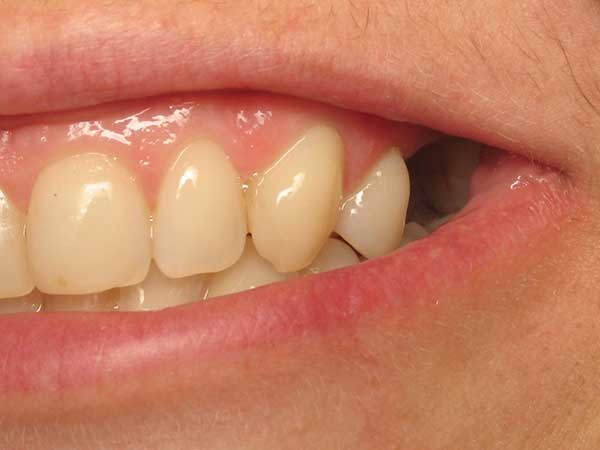

Peggy L.

This patient had broken her tooth and had an Implant placed to replace it.